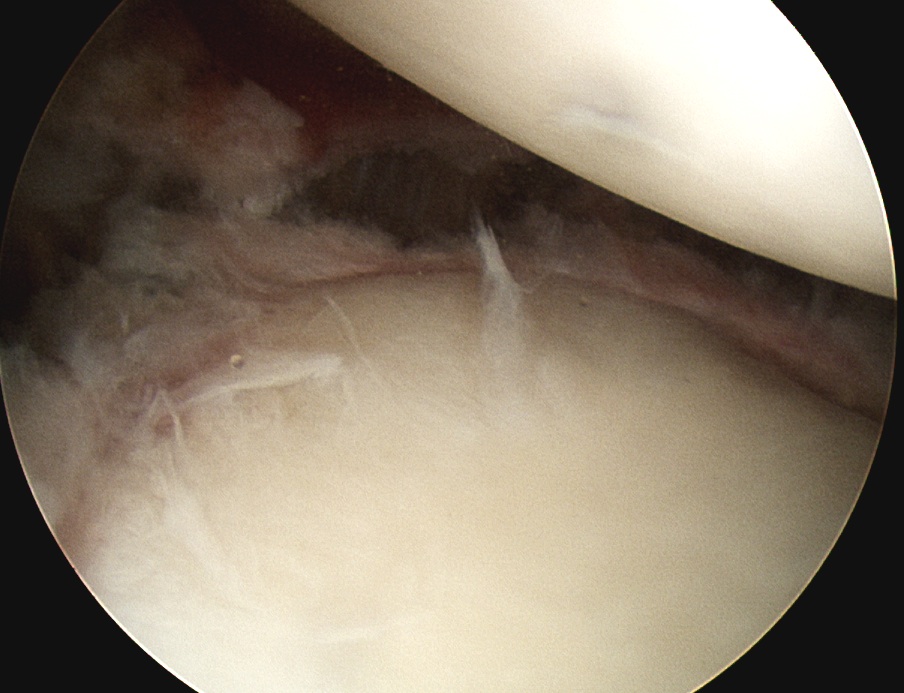

Release posterior IGHL